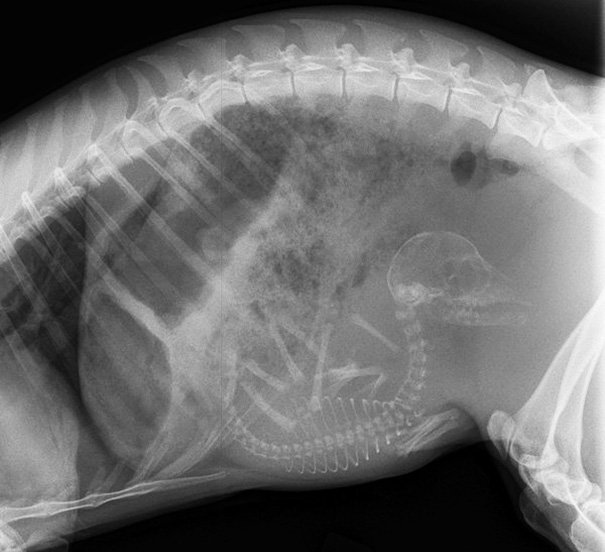

Итак, как выглядят рентгеновские снимки беременных животных:

киви